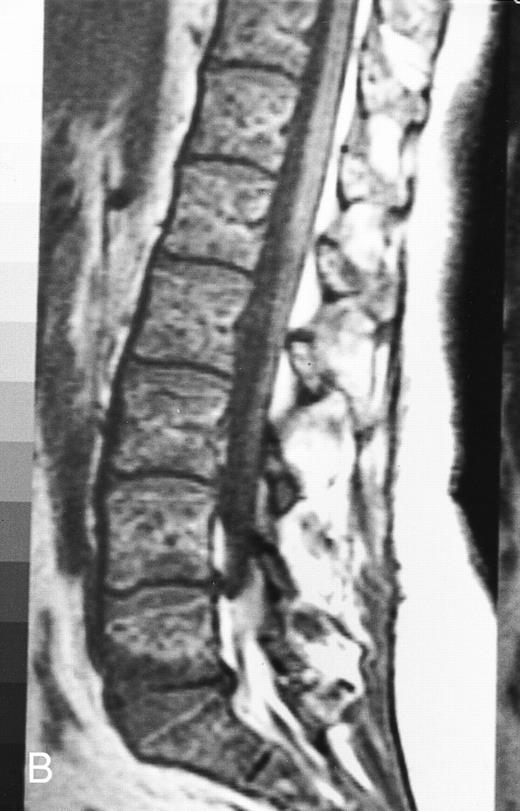

Lymphoma: multifocal bone marrow involvement. Sagittal T1-weighted (500/10, TR/TE) MR image of the lumbar spine shows multiple foci of bone marrow replacement (arrows). This appearance of lymphomatous involvement of the bone marrow is similar to bone metastases. Note extraosseous mass in the presacral space with apparent preservation of the bony cortex and small retroperitoneal lymph node at the level of L2 (arrowheads).